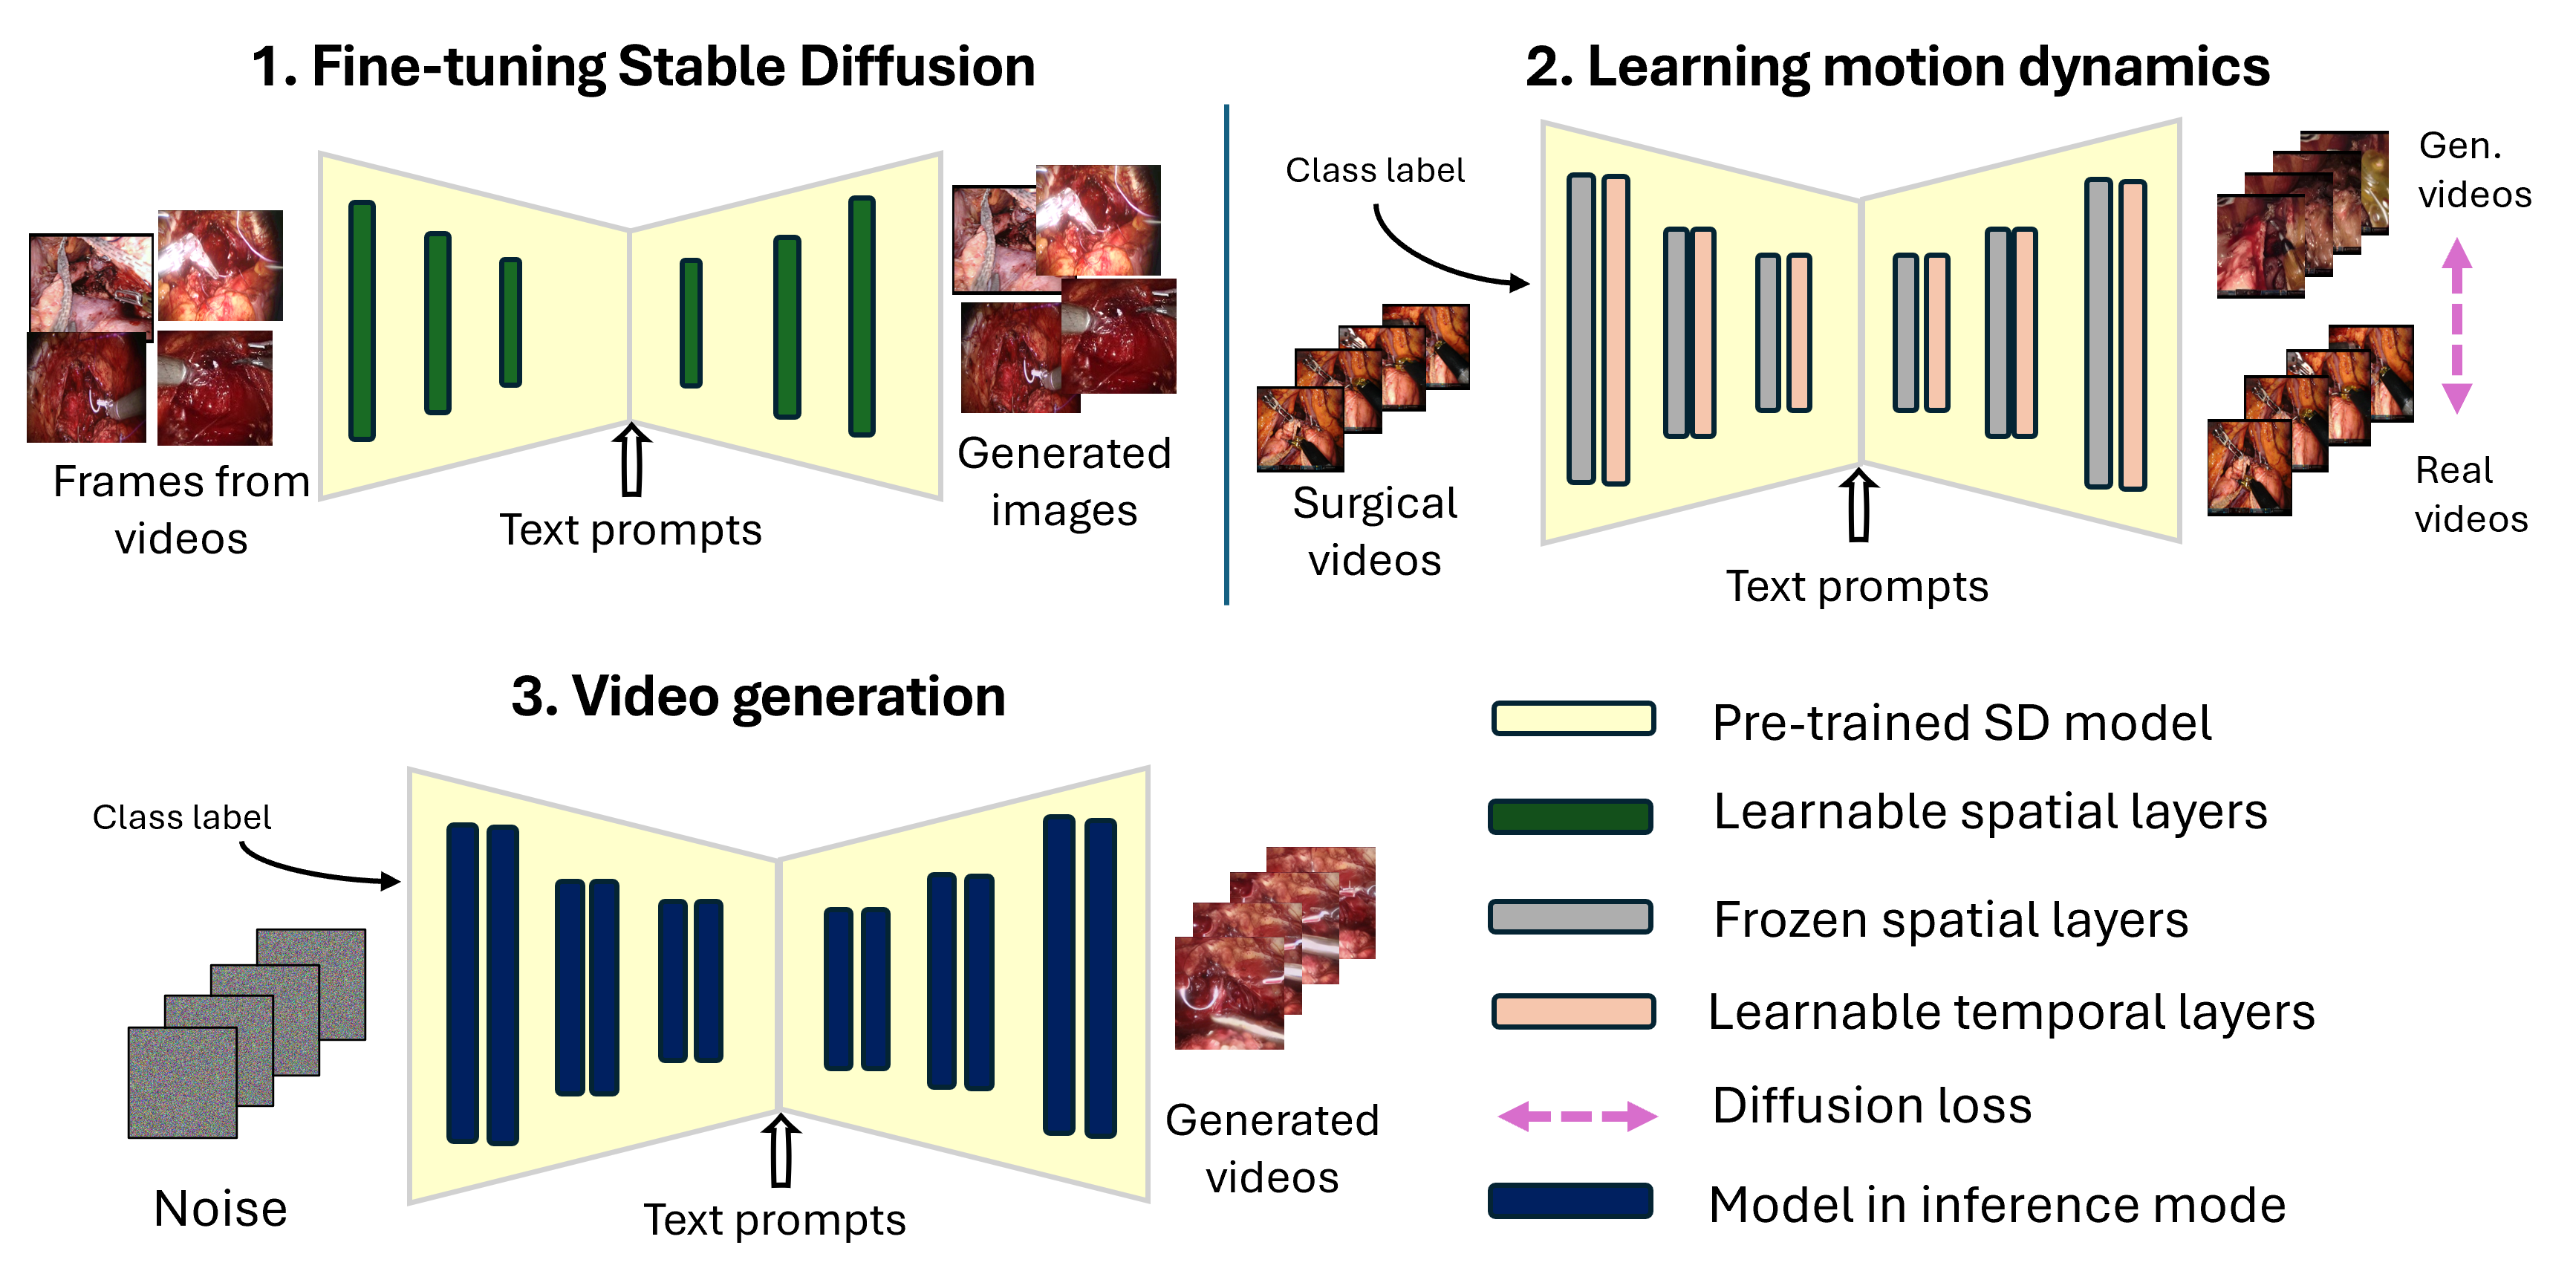

Computer-assisted interventions can improve intraoperative guidance, particularly through deep learning methods that harness the spatiotemporal information in surgical videos. However, the severe data imbalance often found in surgical video datasets hinders the development of high-performing models. In this work, we aim to overcome the data im- balance by synthesizing surgical videos. We propose a unique two-stage, text-conditioned diffusion-based method to generate high-fidelity surgi- cal videos for under-represented classes. Our approach conditions the generation process on text prompts and decouples spatial and temporal modeling by utilizing a 2D latent diffusion model to capture spatial con- tent and then integrating temporal attention layers to ensure temporal consistency. Furthermore, we introduce a rejection sampling strategy to select the most suitable synthetic samples, effectively augmenting exist- ing datasets to address class imbalance. We evaluate our method on two downstream tasks—surgical action recognition and intra-operative event prediction—demonstrating that incorporating synthetic videos from our approach substantially enhances model performance.